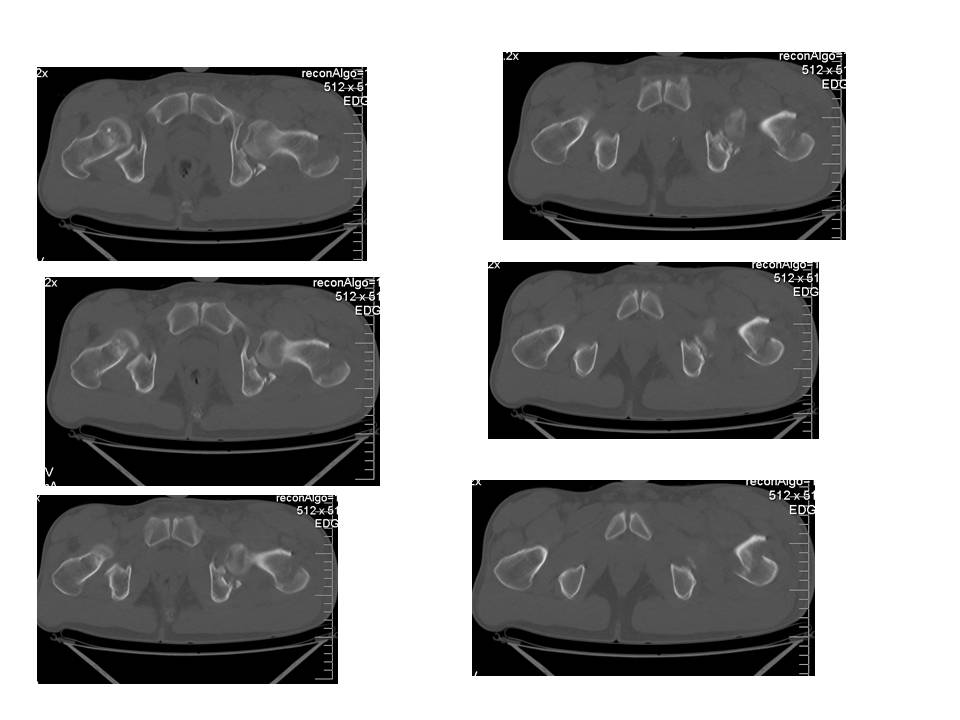

Больной 24 лет, травму получил катаясь на горных лыжах.

На рентгенограммах вертельный перелом. Но при детальном изучении

снимков появилось подозрение на перелом головки бедра. Это побудило

выполнить КТ.

На КТ перелом заднего края вертлужной впадины.